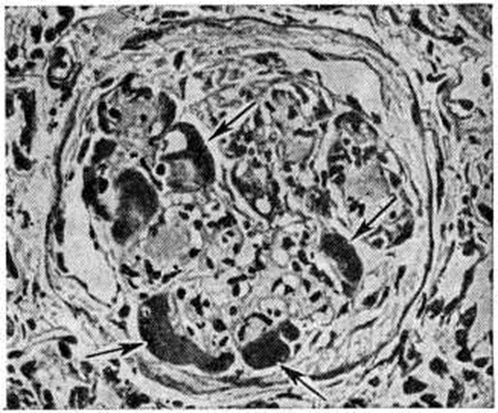

Гломерулосклероз диабетическийГломерулосклероз диабетический (латинское glomerulus клубочек + склероз; греческий diabetes, от diabainein проходить; синонимы: интеркапиллярный гломерулосклероз, синдром Киммелстила — Уилсона) — специфическая и наиболее частая форма поражения почек при сахарном диабете; впервые описана в 1936 году. Гломерулосклероз диабетический является одним из наиболее тяжёлых осложнений сахарного диабета (смотри полный свод знаний Диабет сахарный). Частота Гломерулосклероз диабетический по материалам аутопсии колеблется от 19,5% [Хендерсон (L. Henderson)] до 50,9% [Уайт (White)] у больных, страдающих сахарным диабетом свыше 20 лет. В клинике Гломерулосклероз диабетический, по данным Р. А. Хейфец и Л. И. Каминской, выявляется в 6%, по данным Э. Глоссит Москович — в 17,8% и даже в 48% случаев (В. В. Сура) от числа больных, страдающих сахарным диабетом. У женщин, страдающих сахарным диабетом, Гломерулосклероз диабетический встречается в 30%, у мужчин — в 19,5% случаев. Патологическая анатомияГистологические изменения почек при Гломерулосклероз диабетический весьма полиморфны; выделены три основных формы поражения — узелковая, диффузная и экссудативная. Некоторые авторы вместо экссудативной выделяют смешанную форму. Узелковая форма характеризуется наличием в клубочках эозинофильных образований (узелков) округлой или овальной формы (рисунок 1), содержащих вакуоли. Они могут занимать часть или весь клубочек, по периферии которого в последнем случае располагаются сохранившиеся сдавленные капиллярные петли. Одновременно наблюдается расширение и аневризмы капилляров клубочков, утолщение их базальных мембран. При гистохимическом исследовании узелков они вначале окрашиваются как фибрин, а в дальнейшем как коллаген. Узелки содержат большое количество высокомолекулярных мукополисахаридов, небольшое количество кислых мукополисахаридов, жировых субстанций, в основном ненасыщенных жирных кислот и холестеринэстеров. При электронно-микроскопическом исследовании видно, что формирование узелков происходит в мезангии в виде скопления в нем глыбок и трабекул, сходных с веществом базальной мембраны. Диффузная форма выражается в однородном расширении и уплотнении мезангия с вовлечением в процесс базальных мембран капилляров, которые резко утолщены. Образующиеся в мезангии мембраноподобные структуры не сливаются в сплошные массы, и образования узелков не происходит. Базальные мембраны капиллярных петель клубочков утолщены, структура их исчезает (рисунок 2). Смешанная форма характеризуется сочетанием типичных узелков с диффузным уплотнением мезангия и утолщением базальных мембран капилляров клубочков (рисунок 3). По данным электронно-микроскопических исследований утолщение базальных мембран капилляров клубочков возникает рано, нередко до появления каких-либо клинических проявлений поражения почек, и имеет место, видимо, при всех формах Гломерулосклероз диабетический Утолщение мембран наблюдается не только у больных, но и у молодых людей из диабетически отягощённых семей. Экссудативная форма встречается реже, чем предыдущие, и характеризуется прежде всего так называемый «фибриноидными шапочками», которые представляют собой отложения PAS-положительного материала между эндотелием и базальной мембраной капилляров (рисунок 4). При иммуногистохимическом исследовании в этих образованиях обнаруживается значительное количество комплементсвязывающих иммуноглобулинов, что даёт основание считать их комплексом антиген—антитело, а не сывороточным экссудатом. «Фибриноидные шапочки» не являются специфическими для Гломерулосклероз диабетический, но вместе с тем они обнаруживаются при тяжёлых и быстро прогрессирующих его формах. С ними часто сочетаются так называемый «капсульные капли», располагающиеся на внутренней стороне боуменовой капсулы. |

Рис. 4. | ||